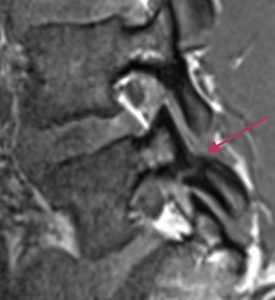

Lannerangan magneettikuva 2

Sivuprofiili, jossa näkyy nikamarakenteita tarkemmin.